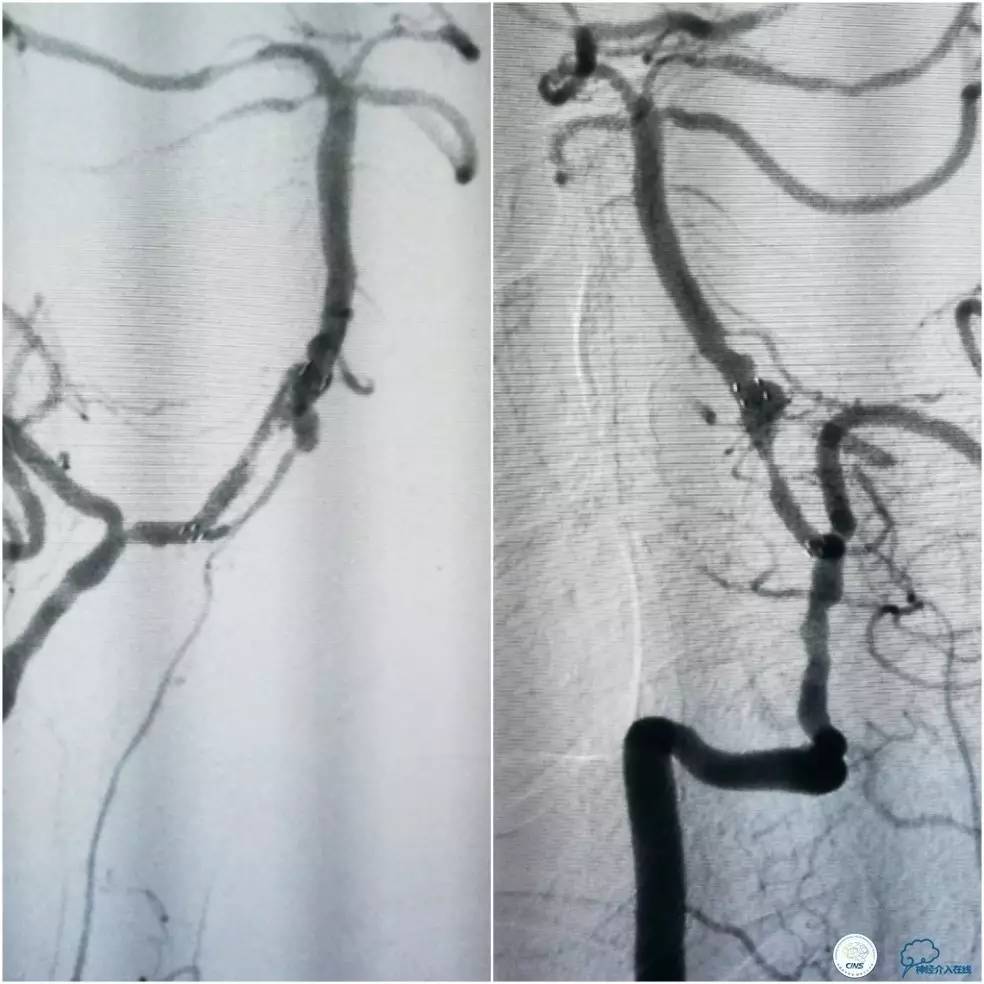

缓慢回撤6F导引导管至锁骨下动脉,造影显示右椎V1段支架无移位,前向血流正常(图17)。

图17

1. 对于后循环合并颅内外串联病变处理序贯,目前尚无统一标准,各有利弊,如考虑近端狭窄程度较重且无明显迂曲的话,可以考虑先处理近端病变(详见第14期)。

2. 本例在近端支架释放完毕后,采用球囊辅助技术顺利的将导引导管越过支架。